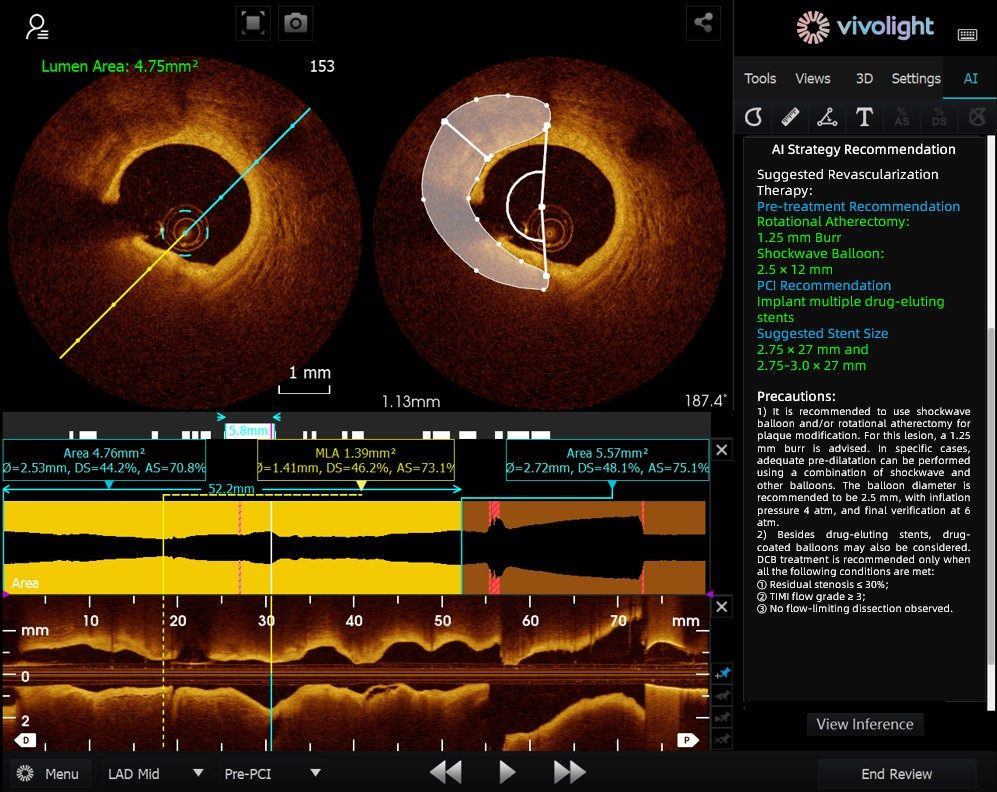

Das auf dem OCT-System von Vivolight Medical basierende AI-OCT ist ein intelligentes Entscheidungsunterstützungssystem der nächsten Generation für die intravaskuläre Bildgebung. Es integriert verstreute intravaskuläre Bildgebungsdaten – darunter Lumendurchmesser, ursächliche Läsionen, OCT-FFR und Plaquebeschaffenheit – in umfassende Behandlungsstrategien und umsetzbare Empfehlungen. Als eigenständige Forschungssoftware, die in die OCT-Plattform integriert ist, wird sie in Zusammenarbeit mit verschiedenen Krankenhäusern entwickelt, um kundenspezifische Versionen für spezifische klinische Bedürfnisse zu erstellen.

Auf dem hochkarätigen Forum betonten Experten, dass das KI-OCT-System einen grundlegenden Wandel von der reinen Bildbetrachtung hin zur Erstellung von Behandlungsplänen darstellt. Es begegnet den Herausforderungen der Informationsflut und der komplexen Entscheidungsfindung bei kardialen Interventionen, die traditionell stark auf der Erfahrung des Arztes beruhen. Zu den wichtigsten Vorteilen des Systems zählen:

●Intraoperative Echtzeitführung: Es organisiert diagnostische Informationen dynamisch während der Operation und liefert wichtige Kennzahlen und klinische Empfehlungen.

●Evidenzbasierte Entscheidungsfindung: Alle Vorschläge entsprechen dem Expertenkonsens und den klinischen Leitlinien, wodurch Strenge und Zuverlässigkeit gewährleistet werden.

Das KI-OCT-System nutzt eine Architektur aus „kleinen Modellen + großen Datenmengen + großen Modellen“: Kleine Modelle ermöglichen eine präzise Bildinterpretation, während große Modelle umfassende klinische Schlussfolgerungen ermöglichen. Durch die Nutzung hochwertiger kardiovaskulärer Datenbanken und der Retrieval-Augmented Generation (RAG)-Technologie bietet es durchgängige Unterstützung von der Läsionsbeurteilung bis zur Entwicklung von Behandlungsstrategien.

Die neu eingeführte Herz-Kreislauf-Datenbank – Chinas erstes nationales Datenbanksystem für Herz-Kreislauf-Erkrankungen – wurde als Grundstein für zuverlässige medizinische KI hervorgehoben. Durch die Integration umfangreicher, qualitativ hochwertiger Daten aus mehreren Zentren löst sie branchenweite Probleme wie isolierte Datenpools und inkonsistente Datenqualität. Experten betonten, dass die Kombination der Datenbankdaten mit fortschrittlichen KI-Algorithmen das Fachwissen führender Ärzte in standardisierte Entscheidungsmodelle übersetzt, einen gleichberechtigten Zugang zu hochwertiger Gesundheitsversorgung fördert und es Hausärzten und jungen Ärzten ermöglicht, eine einheitliche und qualitativ hochwertige Behandlung anzubieten.